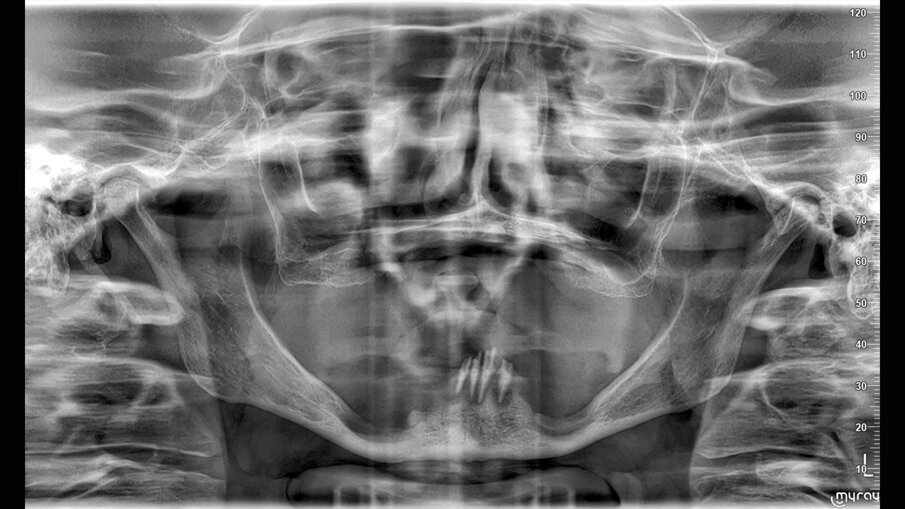

- pianificazione chirurgica della riabilitazione con valutazioni anatomiche, TC Cone-Beam, stereolitografia (SLA), funzionale al progetto protesico;

È presentata una riabilitazione con 4 impianti zigomatici (QUAD) in paziente con grave atrofia del mascellare. In questo caso la protesi con carico funzionale è stata consegnata alla paziente dopo 72 ore. Nelle immagini 1-4 viene mostrata la stereolitografia e la TC della paziente, mentre nelle immagini 5-7 viene mostrata la situazione iniziale e finale della paziente.